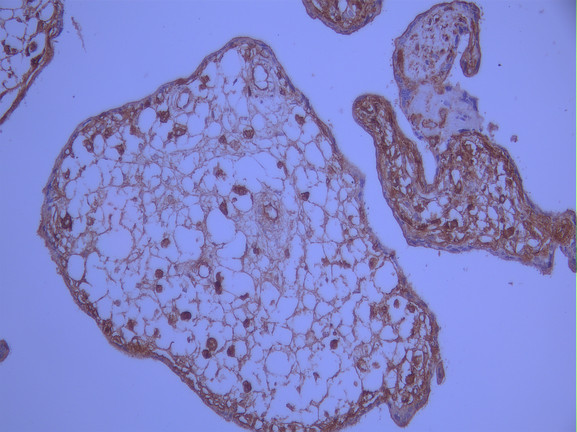

• IHC image of CSB-RA177398A0HU diluted at 1:100 and staining in paraffin-embedded human placenta tissue performed on a Leica BondTM system. After dewaxing and hydration, antigen retrieval was mediated by high pressure in a citrate buffer (pH 6.0). Section was blocked with 10% normal goat serum 30min at RT. Then primary antibody (1% BSA) was incubated at 4°C overnight. The primary is detected by a Goat anti-rabbit polymer IgG labeled by HRP and visualized using 0.05% DAB.